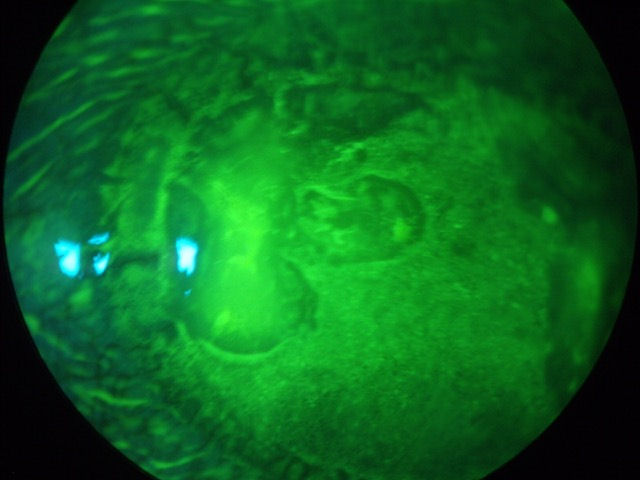

Ниже представлены три фотографии глаза с частично отслоившимся лоскутом LASIK. Пациенту была проведена операция LASIK в 2002 году. Несколько лет спустя на этом глазу сформировалась роговица эктазия , требующий от пациента ношения жестких контактных линз. Из-за незначительной травмы, связанной с контактными линзами, которая для нормального глаза прошла бы без осложнений, лоскут LASIK отделился от роговицы в квадранте с 4:00 до 6:00. Зеленовато-желтый краситель, который был закапан в глаз, проник под лоскут. Этот случай демонстрирует хрупкое состояние роговицы после операции LASIK и доказывает, что лоскут никогда не заживает. (Нажмите на верхнее изображение, чтобы увеличить).